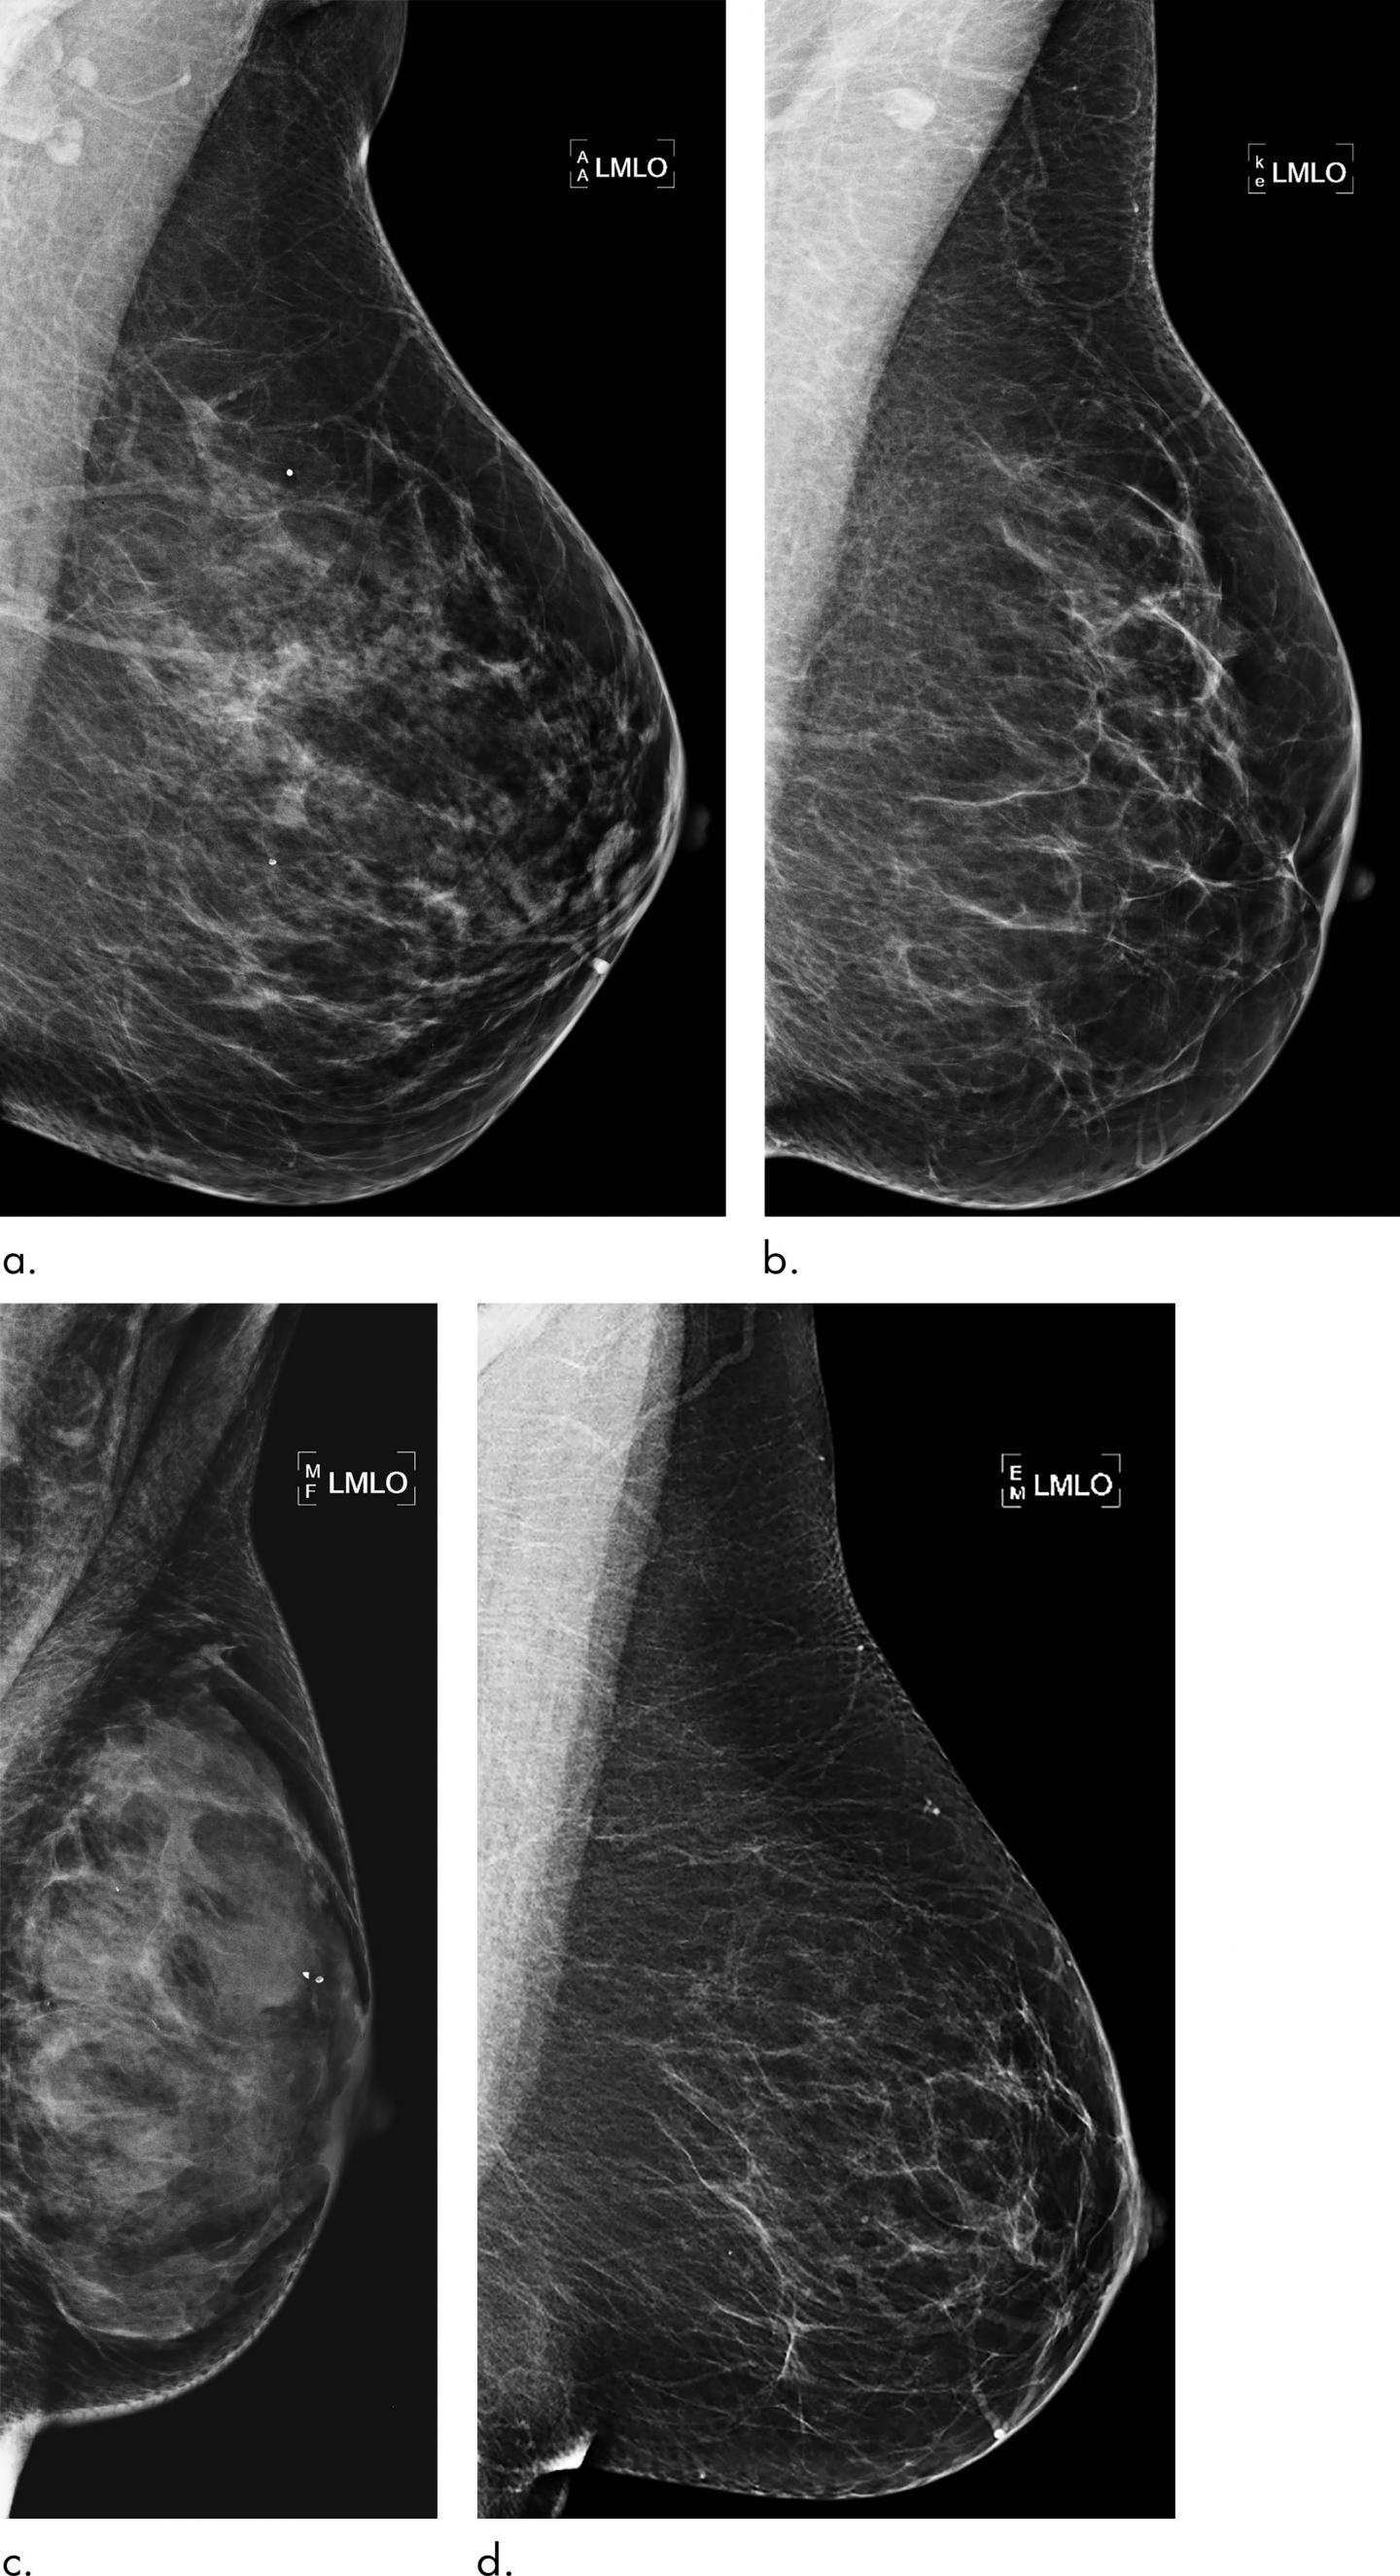

High breast density, or a greater amount of glandular and connective tissue compared to fat, is considered a risk factor for cancer. While density may be incorporated into risk assessment, current prediction models may fail to fully take advantage of all the rich information found in mammograms. This information has the potential to identify women who would benefit from additional screening with MRI.

Dr. Dembrower and colleagues developed a risk model that relies on a deep neural network, a type of AI that can extract vast amounts of information from mammographic images. It has inherent advantages over other methods like visual assessment of mammographic density by the radiologist that may not be able to capture all risk-relevant information in the image.

The new model was developed and trained on mammograms from cases diagnosed between 2008 and 2012 and then studied on more than 2,000 women ages 40 to 74 who had undergone mammography in the Karolinska University Hospital system. Of the 2,283 women in the study, 278 were later diagnosed with breast cancer.

The deep neural network showed a higher risk association for breast cancer compared to the best mammographic density model. The false negative rate--the rate at which women who were not categorized as high-risk were later diagnosed with breast cancer--was lower for the deep neural network than for the best mammographic density model.

"The deep neural network overall was better than density-based models," Dr. Dembrower said. "And it did not have the same bias as the density-based model. Its predictive accuracy was not negatively affected by more aggressive cancer subtypes."